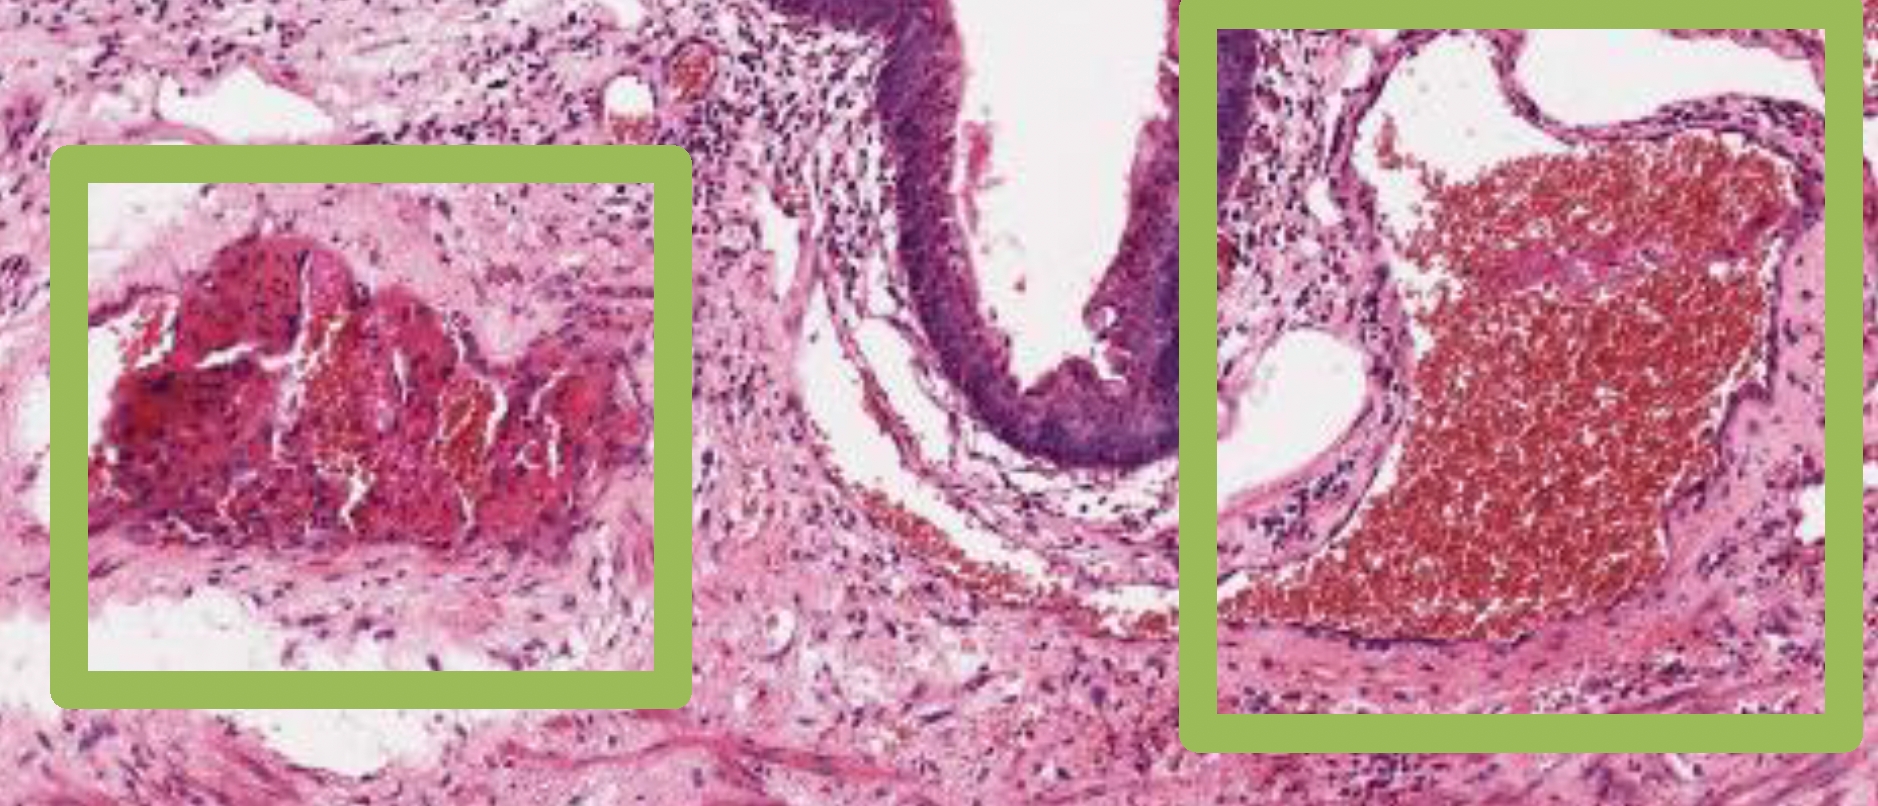

若是血栓形成較久(右圖左),organization會較完整,則血栓內的顏色較淡、fibrin較多、有較多內皮細胞。要與congestion(右圖右,也就是剛形成的fresh thrombus)區分。

fibrin堆積形成的thrombus